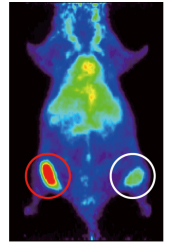

研究グループは、より半減期の短い放射性同位体銅64(64Cu:半減期12.7時間)を用いる新しいPETプローブ「カッパー64・ドータ・トラスツズマブ(64Cu-DOTA-Trastuzumab)」を作製しました。64Cu-DOTA-Trastuzumabが生体内のHER2陽性細胞を検出するかを調べるため、HER2発現量の異なる2種類のヒト腫瘍を移植したマウスでPET検査を行ったところ、移植腫瘍にHER2の発現量を反映した強さのシグナルを認め、PETプローブとしての有用性を確認しました(図1)。また、PET撮像後に取り出した移植腫瘍の顕微鏡観察からも、64Cu-DOTA-TrastuzumabがHER2陽性細胞に結合していることを確認しました。

図1 ヒト腫瘍移植マウスにおけるトラスツズマブPETプローブの集積

マウスにHER2発現レベルの異なる2種類のヒト腫瘍細胞を移植し、64Cu-DOTA-Trastuzumabを用いてPET撮像したところ、HER2発現量の高い腫瘍に顕著なシグナルを観察し(赤丸)、HER2発現量の低い腫瘍では弱いシグナルを観察した(白丸)。なお胴体部の緑の部分は、肝臓への非特異的な蓄積によるもの。